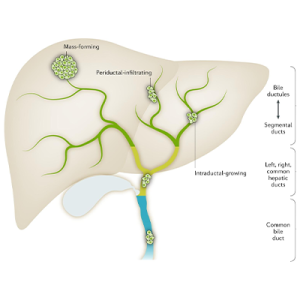

Read MoreHPB – Bile duct

Specialized care for bile duct disorders, including stones, strictures, and...